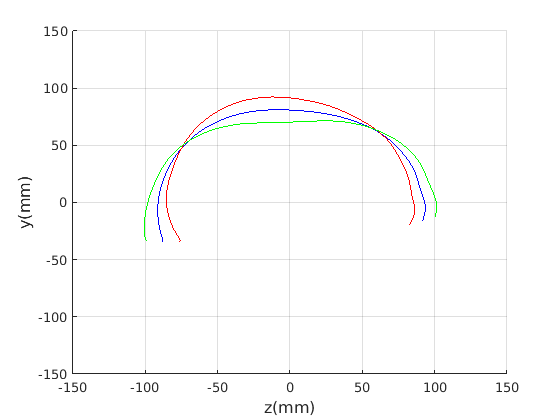

Figure 16 shows examples of the robust ellipse fit for four head profiles. The centre of the ellipse is used in a pose normalisation procedure where the ellipse centre is used as the origin of the profile and the angle from the ellipse centre to the nasion is fixed at -10 degrees. We call this Ellipse Centre - Nasion (ECN) pose normalisation and later compare this to GPA. The major and minor axes of the extracted ellipses are plotted as red and green lines respectively in Fig. 16.

|

Figure 17 shows all 100 profiles overlaid with the same alignment scheme. The median value of major ellipse axis and the ellipse centre-nasion angle differ by 3.6 degrees, so that when the nasion angle is fixed at -10 degrees, the median ellipse angle is -6.4 degrees (cf. -7.4 degrees with manual landmarking of the nasion). We noted regularity in the orientation of the fitted ellipse as is indicated by the clustering of the major (red) and minor (green) axes in Fig. 17 and the histogram of ellipse orientations in Fig. 18. For most people, the major axis of the ellipse is closely aligned with the y-axis (upright), and titled slightly forwards. A minority of heads (9%) in the training sample have their major ellipse axes closer to the vertical (these relatively tall and short heads are known as brachycephalic.) Ellipse axis clustering (relative to the fixed ellipse centre-nasion line) does not appear to be sharply defined. This is because many crania are close to circular in cross-section, making the orientation of these angles sensitive to small changes in shape from one person to the next. Note also the variation at the back of the head due to a variety of hair styles, some of which protrude from under the cap. We limit the region over which we model the cranial shape in order to crop this unwanted data out.